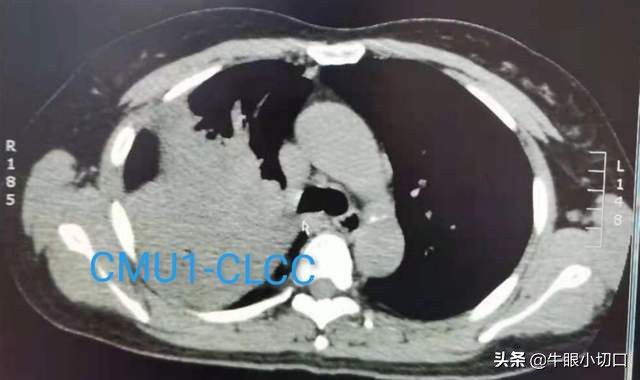

肺CT提示大瘤子占据上半胸、肺门部,来自右上叶,已侵及右主支气管、右中间干,右上肺动脉支已被瘤子包绕,其起始部已受侵,右肺动脉干已受压变形,部分被瘤包绕或已直接受侵袭。纵隔淋巴结成串肿大,怀疑转移。病期相对较晚。

进一步做超声-纤维支气管镜检查,确认瘤子来自右上叶,侵及二级隆突,侵及右主支气管远端,取材病理提示为肺鳞癌,隆突下淋巴结转移。

初步检查后评估,目前瘤大、靠肺门、靠根儿、明确有纵隔淋巴结转移,但尚没有远隔转移,属于局部晚期病例。